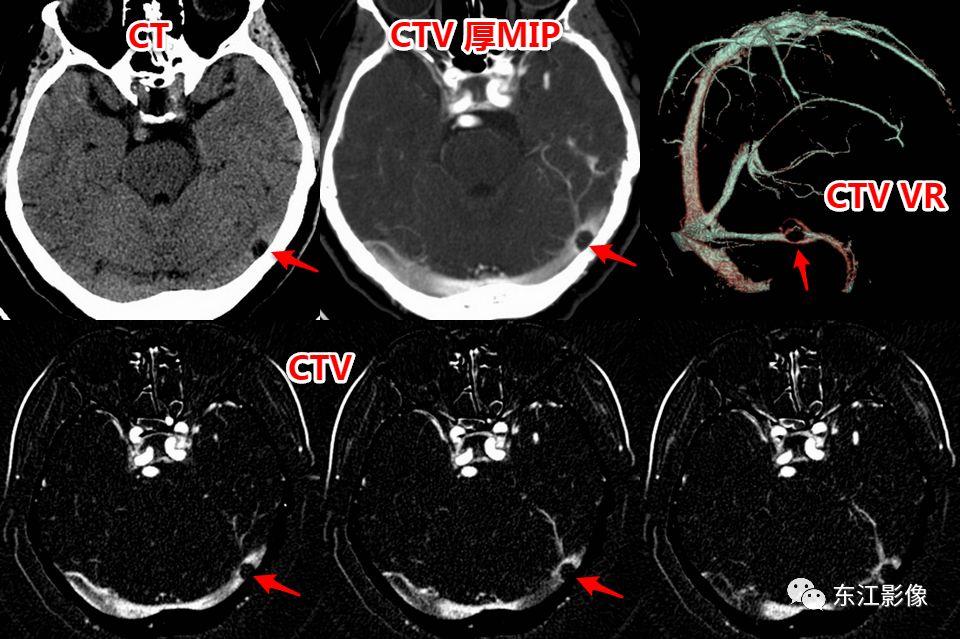

2. 静脉窦内扩大的蛛网膜颗粒

- 以横窦常见(横断面图像最容易被发现的缘故),其次为上矢状窦,直窦、乙状窦少见,海绵窦罕见。

- CT平扫,呈稍高密度背景内低密度充盈缺损。

- MRI T1WI为低信号,稍高于脑脊液信号;T2WI为高信号,FLAIR多为低信号,稍高于脑脊液信号,较大的其内可见絮状稍高信号;增强多无强化,较大的其内可见点、线状强化灶。MRV上均呈附壁状充盈缺损。

- 极少数静脉窦内扩大的蛛网膜颗粒可能会引起静脉窦狭窄,DSA实时压力测量是确诊工具。

右侧横窦扩大的蛛网膜颗粒。

左侧横窦扩大的蛛网膜颗粒。